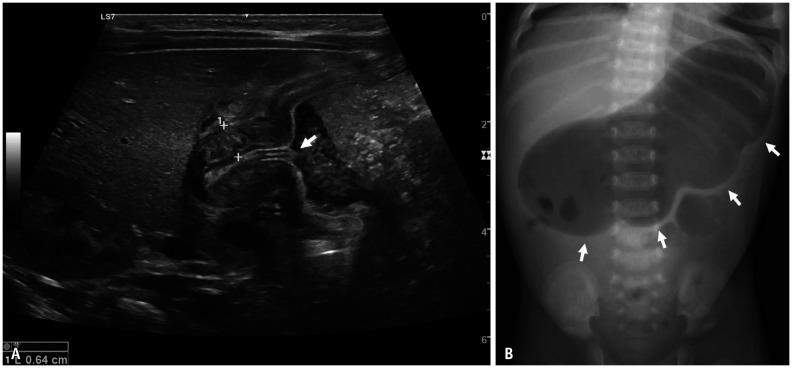

Gastrointestinal (GI) emergencies in neonates and infants encompass from the beginning to the end of the GI tract. Both congenital and acquired conditions can cause various GI emergencies in neonates and infants. Given the overlapping or nonspecific clinical findings of many different neonatal and infantile GI emergencies and the unique characteristics of this age group, appropriate imaging is key to accurate and timely diagnosis while avoiding unnecessary radiation hazard and medical costs. In this paper, we discuss the radiological findings of essential neonatal and infantile GI emergencies, including esophageal atresia and tracheoesophageal fistula, hypertrophic pyloric stenosis, duodenal atresia, malrotation, midgut volvulus for upper GI emergencies, and jejunoileal atresia, meconium ileus, meconium plug syndrome, meconium peritonitis, Hirschsprung disease, anorectal malformation, necrotizing enterocolitis, and intussusception for lower GI emergencies.

新生儿和婴儿的胃肠道(GI)急症涵盖了从胃肠道的开始到结束的各个方面。先天性和后天性疾病都可能导致新生儿和婴儿出现各种胃肠道急症。鉴于许多不同的新生儿和婴儿胃肠道急症的临床发现具有重叠或非特异性,以及该年龄段的独特特征,适当的影像学检查对于准确和及时的诊断至关重要,同时避免不必要的辐射危害和医疗费用。在本文中,我们讨论了基本的新生儿和婴儿胃肠道急症的放射学表现,包括食管闭锁和食管气管瘘、肥厚性幽门狭窄、十二指肠闭锁、肠旋转不良、胃上消化道急症,以及空肠回肠闭锁、胎粪性肠梗阻、胎粪栓综合征、胎粪性腹膜炎、先天性巨结肠、肛门直肠畸形、坏死性小肠结肠炎和肠套叠等下消化道急症。